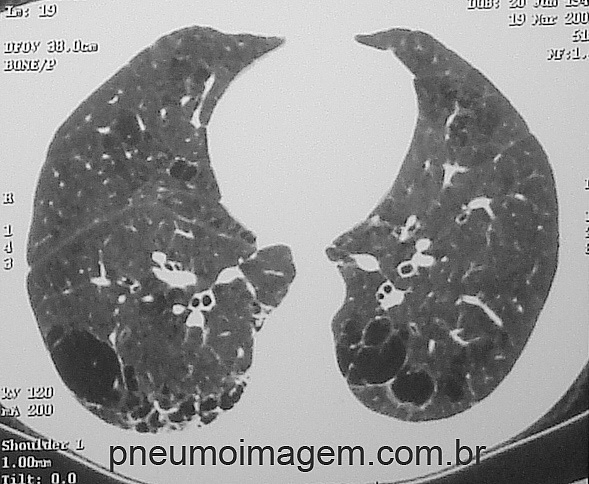

Clique aqui para ver imagens tomográficas de DPOC no PneumoImagem.